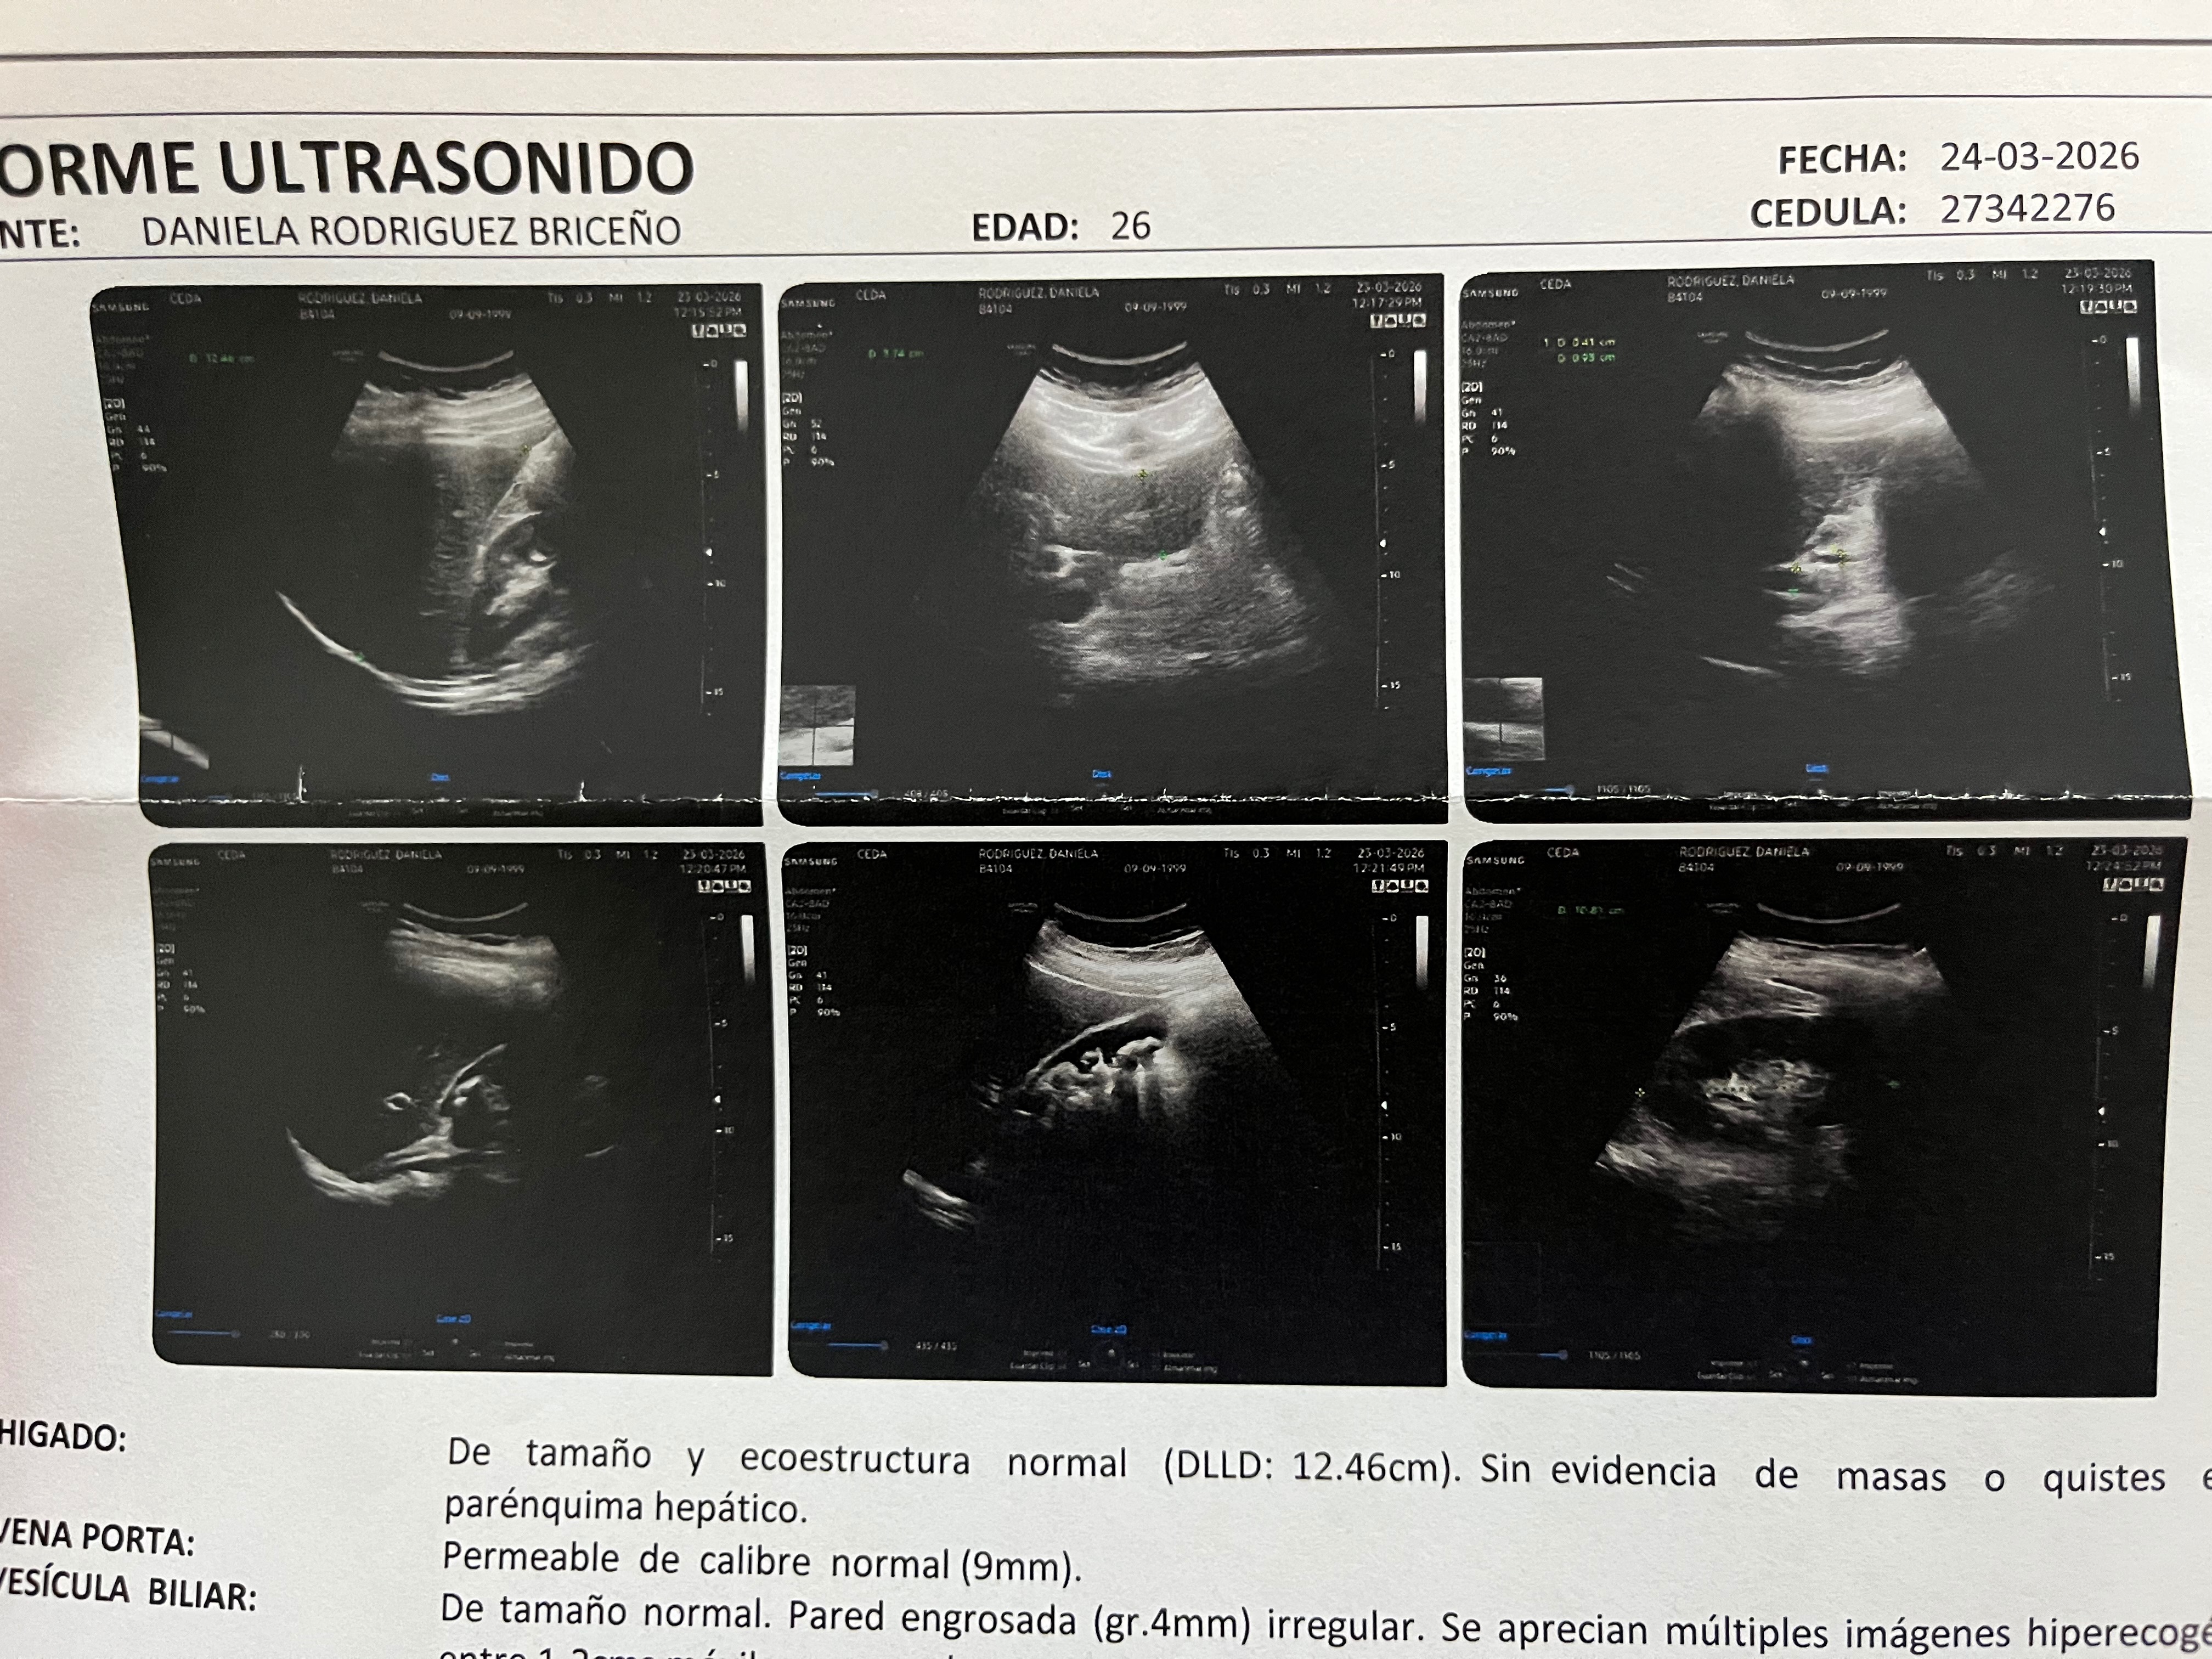

Hace dos semanas el dolor empezó a ponerse cada vez más intenso, tenía cólicos terribles y dejé de tolerar casi todo lo que comía; al acudir de emergencia al médico me hicieron todos los estudios y descubrieron que tengo cálculos en la vesícula acompañados de una inflamación importante con engrosamiento de pared, y me dieron el diagnóstico de colecistitis crónica y litiasis vesicular múltiple.

Two weeks ago the pain began to get more and more intense, I had terrible cramps and stopped tolerating almost everything I eat; when I went to the doctor urgently they did all the studies and discovered that I have gallstones accompanied by a significant inflammation with thickening of the wall, and they gave me the diagnosis of chronic cholecystitis and multiple vesicular lithiasis.